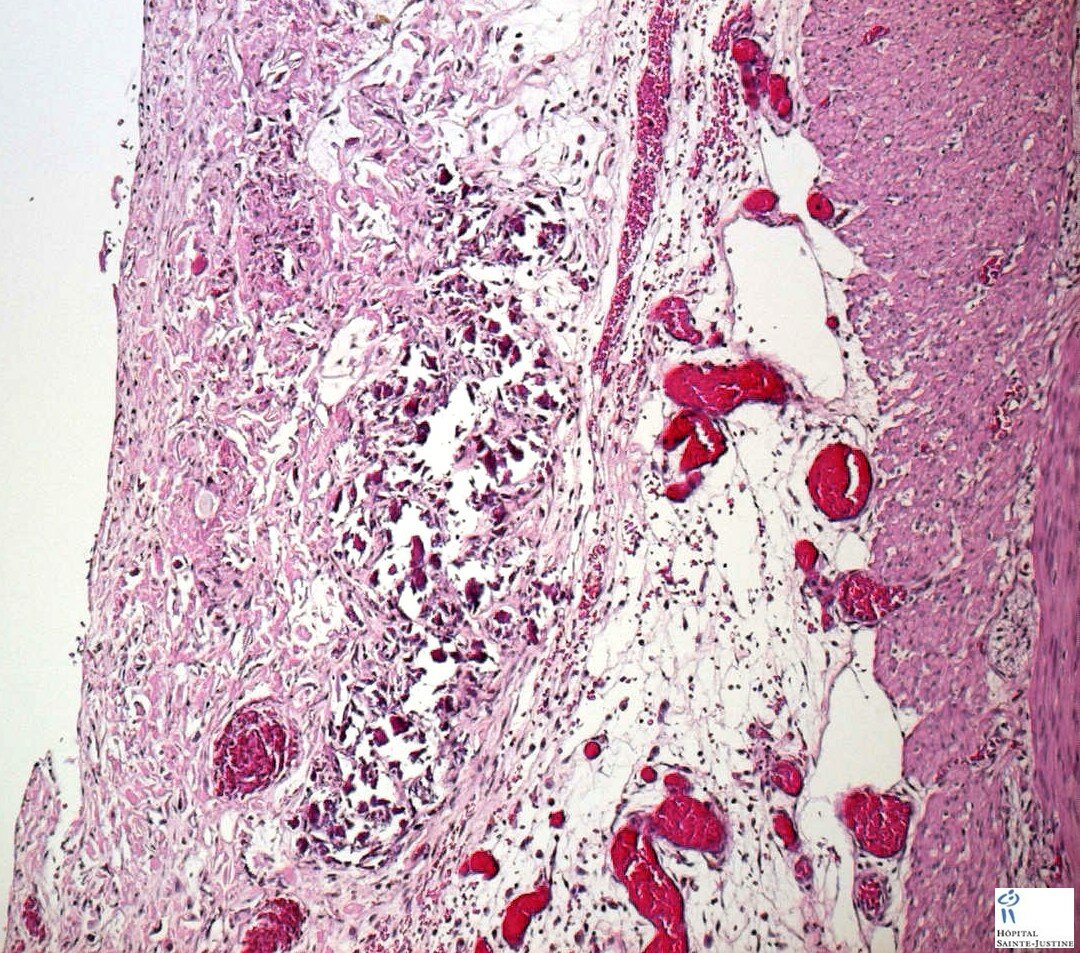

Meconial peritonitis in fetal cystic fibrosis